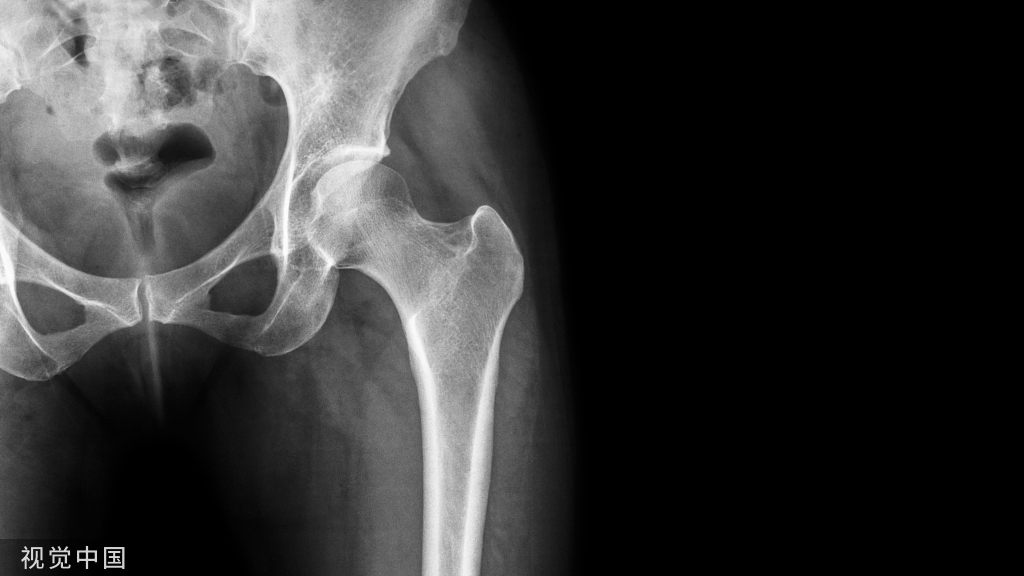

4复位之后需要进行X线的检查,